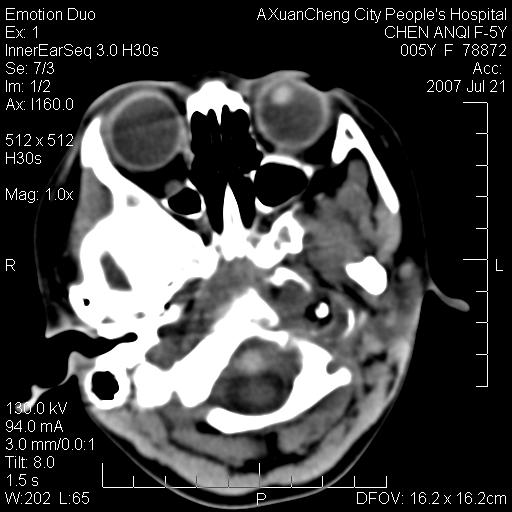

标题: PED0273:5岁,左耳流脓痛疼一周,颅底骨质破坏 [打印本页]

标题: PED0273:5岁,左耳流脓痛疼一周,颅底骨质破坏

患儿5岁,左耳流脓痛疼一周,左外耳道肉芽组织填塞 软组织窗显示病灶内结节状低密度影为气体密度

1.左耳中耳炎. 2.考虑伴颅内感染.

颅底骨质破坏,建议增强扫描

左侧中耳炎并胆脂瘤,左颞骨岩部骨质破坏并颅内感染积气。

考虑化脓性中耳乳突炎伴胆脂肪瘤形成并左颞叶感染,不除外合并嗜酸性肉芽肿.